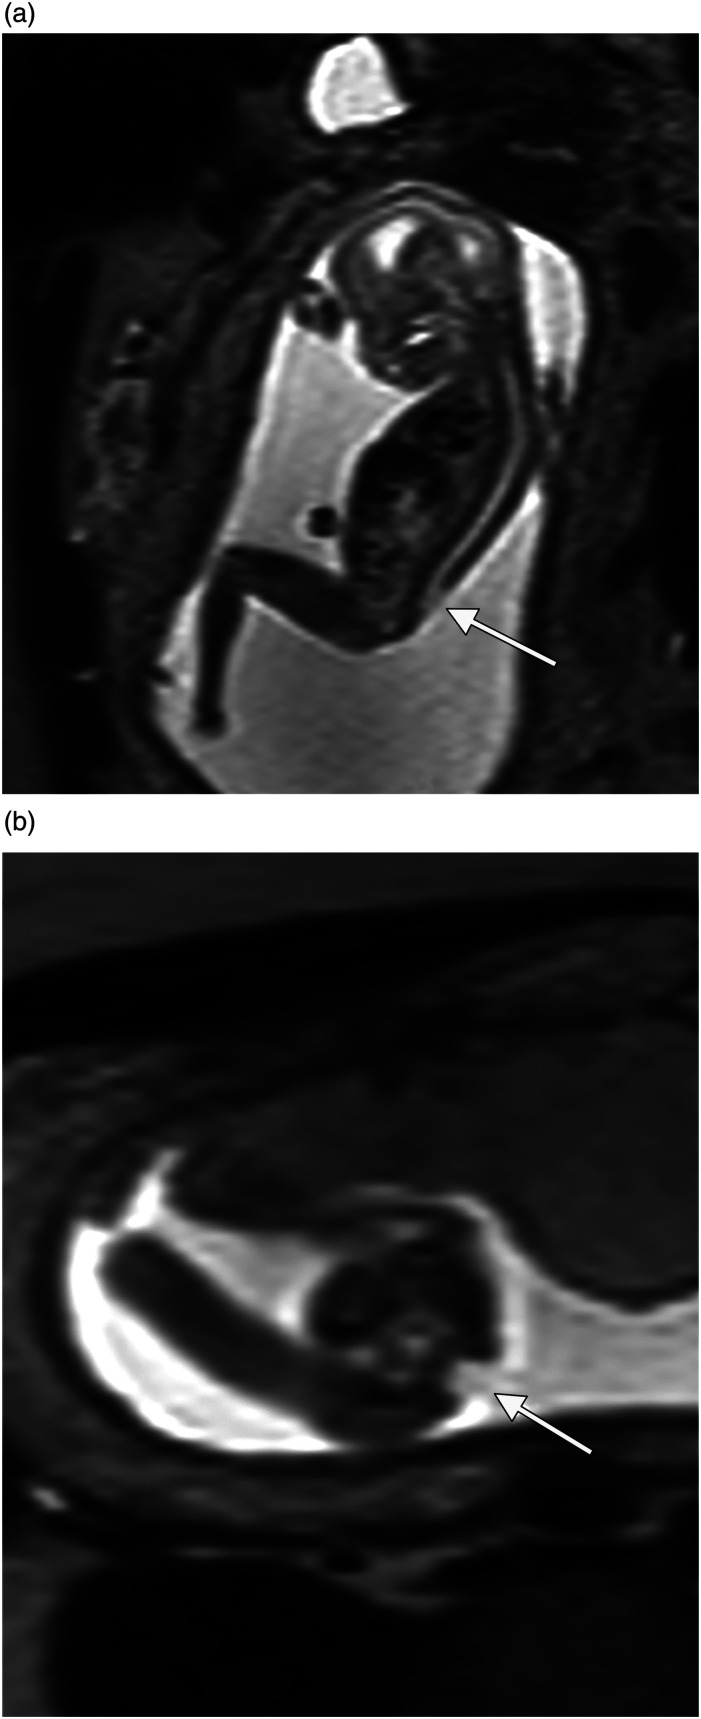

背景:胎儿超声波检查有其局限性,尤其是在患者肥胖或胎粪过少的情况下。核磁共振成像(MRI)可作为补充,但只有少数研究关注妊娠后三个月的检查。目的:验证核磁共振成像作为诊断妊娠后三个月胎儿畸形的补充:这项回顾性研究检索了乌普萨拉大学医院胎儿医学科和放射科 2008 年 1 月至 2012 年 7 月的数据。研究回顾了 121 个胎儿的超声和磁共振成像结果与最终诊断的关系,包括产后随访和尸检结果:结果:在 121 个胎儿中,51 个(42%)确诊或怀疑有中枢神经系统异常,70 个(58%)确诊或怀疑有非中枢神经系统异常。在所有病例中,核磁共振成像为21%的病例提供了额外的信息,但并未改变妊娠管理,而为13%的病例提供的信息改变了妊娠管理。当发现或怀疑中枢神经系统异常时,核磁共振成像为 22% 的病例提供了补充信息,改变了 10% 的病例的治疗方案。非中枢神经系统病例的相应数字分别为 21% 和 16%。在体重指数(BMI)大于 30 kg/m2 的患者(25%)和少腹水患者(38%)中,提供额外信息并改变处理方案的病例比例尤其高。在 5 例 III 类病例中,发现了假阳性超声检查结果:结论:妊娠后三个月的核磁共振成像是超声检查的补充,可提高对胎儿中枢神经系统和非中枢神经系统畸形的诊断率,尤其是在少子水肿或孕妇肥胖的情况下。

Conclusions: MRI in the second trimester complements ultrasound and improves diagnosis of fetal CNS- and non-CNS anomalies especially when oligohydramnios or maternal obesity is present.